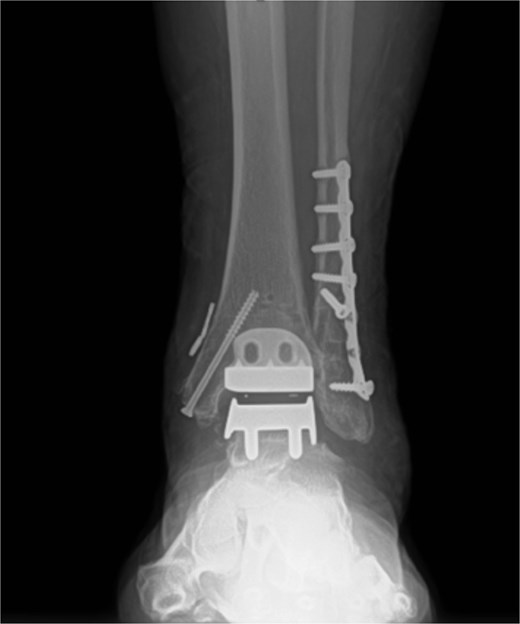

Excellent maintenance of intra-operative range of motion was observed after surgery (Fig. 3a and b), with significant decreases in pain and no ectopic bone formation noted on radiographs at the most recent follow-up at 1 year post-surgery (Fig. 4). Visual analog pain scale (VAS), American Orthopedic Foot and Ankle Society score (AOFAS), and foot function index (FFI) were recorded before surgery and again at the 1-year follow-up. The pre-operative VAS, AOFAS, and FFI were recorded as 10, 24, and 85.9, respectively. The example patient improved in all measures when compared to pre-operative values, with post-operative VAS, AOFAS, and FFI of 1, 90, and 9.7, respectively.

Post-operative radiograph without any sign of gutter impingement or ectopic bone formation.